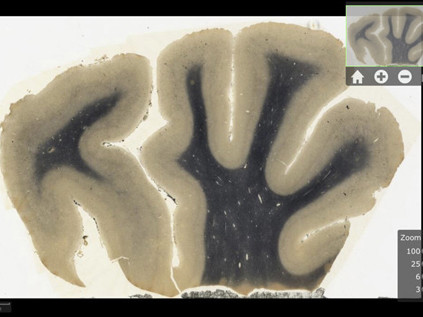

| Một lát cắt não của Einstein trong ứng dụng mới dành cho máy tính bảng iPad. Ảnh: AP. |

Bảo tàng Y tế và Dược phẩm Quốc gia Mỹ - đang được xây dựng tại thành phố Chicago, bang California, Mỹ - đã quét và số hóa gần 350 lát cắt từ não của Einstein sau khi ông qua đời vào năm 1955.

Ứng dụng mới cho phép các nhà nghiên cứu, giáo viên, sinh viên và nhiều đối tượng khác chiêm ngưỡng bộ não của nhà vật lý thiên tài mà không cần phải dùng kính hiển vi.

Harvey đã đưa các lát cắt não của Einstein cho các nhà khoa học để họ thực hiện một nghiên cứu. Kết quả nghiên cứu, được công bố trên tạp chí Lancet vào năm 1999, cho thấy thùy đỉnh của Einstein rộng hơn người bình thường tới 15%.

Thùy đỉnh, nằm trên đỉnh đầu, là nơi kiểm soát cảm giác không gian và định hướng, giúp con người xác định vị trí của các vật thật hoặc tưởng tượng. Nó có vai trò quan trọng đối với hoạt động học toán, ngôn ngữ.

Tiến sĩ Philip Epstein, một nhà khoa học thần kinh tại Chicago, nói rằng ứng dụng của Landers cho phép người sử dụng khám phá sâu hơn vào não của Einstein bằng cách quan sát những vùng não mà số các kết nối giữa tế bào thần kinh lớn hơn mức bình thường.

Nhưng do não của Einstein bị cắt thành những lát trước khi các công nghệ hình ảnh hiện đại được phát minh nên các nhà khoa học không thể xác định mỗi lát tới từ đâu.

"Hồi đó công nghệ chụp ảnh cộng hưởng từ chưa ra đời nên chúng tôi không có phiên bản ba chiều của não Einstein. Vì thế chúng ta không thể xác định được vị trí ban đầu của các lát cắt", Jacopo Annese, nhà nghiên cứu thần kinh của Đại học California tại Mỹ, phát biểu.